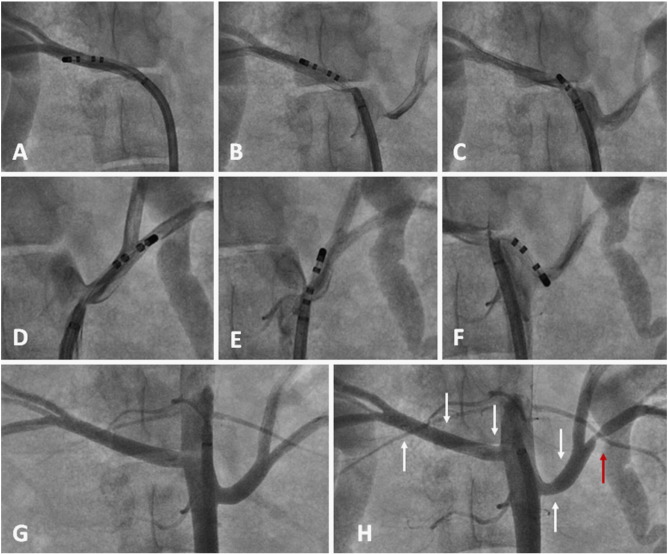

Fig. 1

Fig. 1.

Example of renal denervation in Pig 6 (Protocol 1) with the long sheath Agilis® and gold 4 mm non-irrigated tip catheter. Within the right artery (5.8 mm diameter): A — first (distal) lesion with 8 W; B — second (middle) lesion with 5 W; C — third (proximal) lesion with 8 W. Within the left artery (5.6 mm diameter): D — first (distal) lesion inside a small branch (2.1 mm diameter) with 8 W; E — second (middle) lesion with 5 W; F — third (proximal) lesion with 5 W. G — Non-selective angiography before ablation. H — Angiography after the entire set of lesions showing severe stenosis (80%) in the left inferior small branch after bifurcation (red arrow).